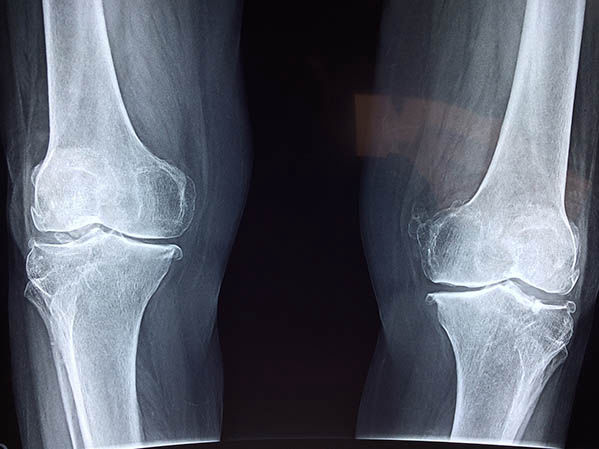

Gyakran alkalmaznak ilyenkor röntgent, ultrahangot, CT-t vagy MRI vizsgálatot egyaránt.

Fontos, hogy megállapítsák a sérülés súlyosságát